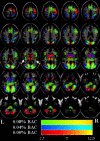

We examined the effects of two doses of alcohol (EtOH) on functional magnetic resonance imaging (fMRI) activation during a visual perception task. The Motor-Free Visual Perception Test-Revised (MVPT-R) provides measures of overall visual perceptual processing ability. It incorporates different cognitive elements including visual discrimination, spatial relationships, and mental rotation. We used the MVPT-R to study brain activation patterns in healthy controls (1) sober, and (2) at two doses of alcohol intoxication with event-related fMRI. The fMRI data were analyzed using a general linear model approach based upon a model of the time course and a hemodynamic response estimate. Additionally, a correlation analysis was performed to examine dose-dependent amplitude changes. With regard to alcohol-free task-related brain activation, we replicate our previous finding in which SPM group analysis revealed robust activation in visual and visual association areas, frontal eye field (FEF)/dorsolateral prefrontal cortex (DLPFC), and the supplemental motor area (SMA). Consistent with a previous study of EtOH and visual stimulation, EtOH resulted in a dose-dependent decrease in activation amplitude over much of the visual perception network and in a decrease in the maximum contrast-to-noise ratio (in the lingual gyrus). Despite only modest behavior changes (in the expected direction), significant dose-dependent activation increases were observed in insula, DLPFC, and precentral regions, whereas dose-dependent activation decreases were observed in anterior and posterior cingulate, precuneus, and middle frontal areas. Some areas (FEF/DLPFC/SMA) became more diffusely activated (i.e., increased in spatial extent) at the higher dose. Alcohol, thus, appears to have both global and local effects upon the neural correlates of the MVPT-R task, some of which are dose dependent.